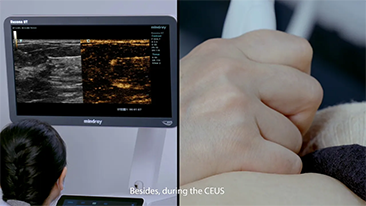

Bir karaci?er ne kadar net g?rĂŒlebilir?

Hemanjiyom veya karaci?er kanseri gibi fokal karaci?er lezyonlar? i?in, ultrason kontrast g?rĂŒntĂŒlemesi ?nemli bir rol oynar. Ultra geni? lineer olmayan UWN+ kontrast g?rĂŒntĂŒleme teknolojisi, daha dĂŒ?ĂŒk MI ve daha uzun perfĂŒzyon sĂŒresi g?zlemi ile daha iyi penetrasyon, daha yĂŒksek kontrast doku oran? elde edilmesine yard?mc? olabilir.